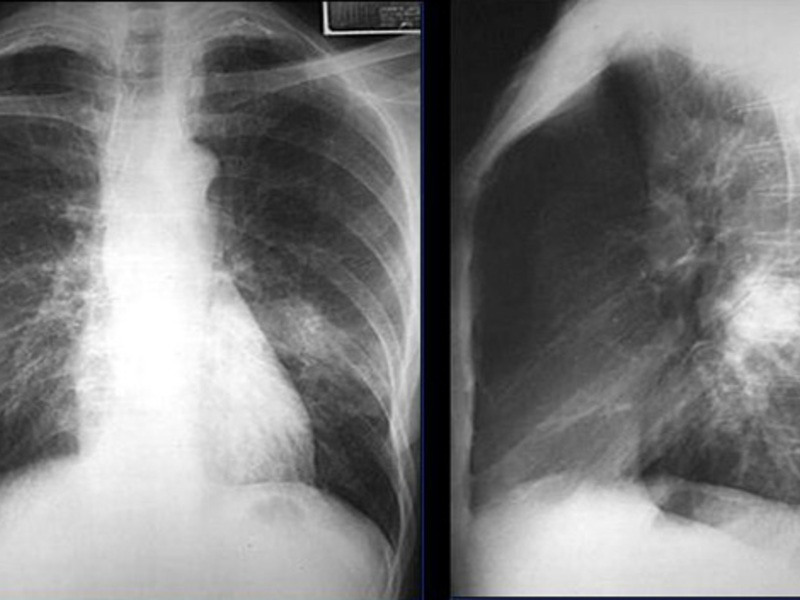

Атипичная пневмония — собирательный термин, включающий инфекционно-воспалительные поражения тканей лёгких. Причинами являются нехарактерные возбудители — микоплазма, хламидия, легионелла, вирусы. Воспаление лёгких протекает с повышением температуры, одышкой, общим недомоганием.

Диагностировать патологический процесс можно при помощи рентгена. Так, для микоплазменной формы характерна неоднородная инфильтрация лёгочной ткани, она может определяться слабо или быть среднеинтенсивной.

При легионеллезной, на снимке видно уплотнения (инфильтраты) округлой формы, локализующиеся на поверхности одной доли лёгкого. В ряде случаев наблюдается слияние инфильтратов. У 25% пациентов одновременно с пневмонией определяется плеврит, с незначительным скоплением секрета в плевральной полости.

Правосторонняя бронхо- пневмония

Практически невозможно отличить пневмонию Legionella от других, основываясь на таком методе обследования. Присутствие легионеллы или хламидии подтверждается серологическим анализом крови.

Отдельное внимание стоит уделить воспалению неинфекционной этиологии. Одна из таких форм — инфаркт-пневмония, развивающаяся на фоне тромба, попавшего из лёгочной артерии в лёгкое. На рентгеновском изображении выступает как очаговое поражение с относительно чётким контуром.

Атипичная пневмония на рентгене

Атипичная форма болезни характеризуется тем, что ее клиническая картина не соответствует картине на рентгеновском снимке. Это создает некоторые трудности при постановке точного диагноза.

Самый яркий пример атипичной пневмонии – микоплазменная форма болезни. На снимке она проявляется значительным очагом поражения. В патологический процесс вовлекается целая доля. Однако, при этом температура тела у пациента повышается незначительно. Кашель его не душит. Вместо болей в легких он жалуется на боль в горле.

Особняком стоят неинфекционные пневмонии. Например, инфаркт-пневмония. Эта форма болезни развивается из-за проникновения в легкое тромба из легочной артерии. На снимке такое поражение имеет четкие контуры, из-за чего его можно спутать с инородным телом в легких.